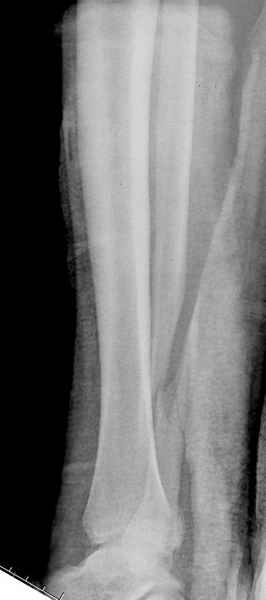

>На сделанных у нас снимках видно, что не все благополучно...

Неравномерность суставной щели может быть связана с разрывом глубокой порции дельтовидной связки и ротацией м/берцовой кости за счет поврежденных структур синдесмоза(репозиция ее на уровне перелома как-будто удовлетворительная).

По моему мнению,ассиметрия суставной щели обусловлена импрессией медиальной части суставной поверхности б/б кости. Да, позиционный винт здесь не лишен, но через 4 недели целесообразность его проведения сомнительна, брейс, ограничение осевой нагрузки достаточно.Есть еще деонтологические аспекты повторной операции, не все так плохо выполнено предыдущим доктором!

Импрессия медиальной части суставной поверхности бывает при супинационном механизме перелома лодыжек (тип А по классификации АО). Здесь механизм пронациия+наружная ротация (тип С, синдесмоз и межкостная мебрана повреждены),

перелом медиальной лодыжки отрывной, при этом в 20-30% бывает повреждение дельтовидной связки.

Клиновидность щели сустава следствие повреждения дельты, невосстановления длины малоберцовой или (хотел сказать "установки в гипсе", но оного, вроде,

нет)? Устранить бы причину. А равно как и тенденцию" к наружному подвывиху. Чрескостный остеосинтез - метод выбора.

Мое мнение, что никакой ротации малоберцовой кости здесь нет и синдесмоз тоже впорядке. Все дело в некачественно репозиции медиального мыщелка. Скорее всего его или немного ротировали при операции или сместили латерально. Более склонен ко второму варианту.

При реконструкции голеностопа, о важности восстановления длины малоберцовой для профилактики пост травматического артроза разбирали в предыдущих дискуссиях. Нарушенную биомеханику голеностопа без восстановления длины малоберцовой, не восстановить только швом медиальной связки.

Расширенная медиальная щель более чем на 4 мм и укорочение малоберцовой более чем 2 мм, а перелом заднего края большеберцовой смещения более 2мм с вовлечением 30% поверхности сустава, считается отходом от нормы голеностопного сустава, и подлежит к оперативному вмещательству.